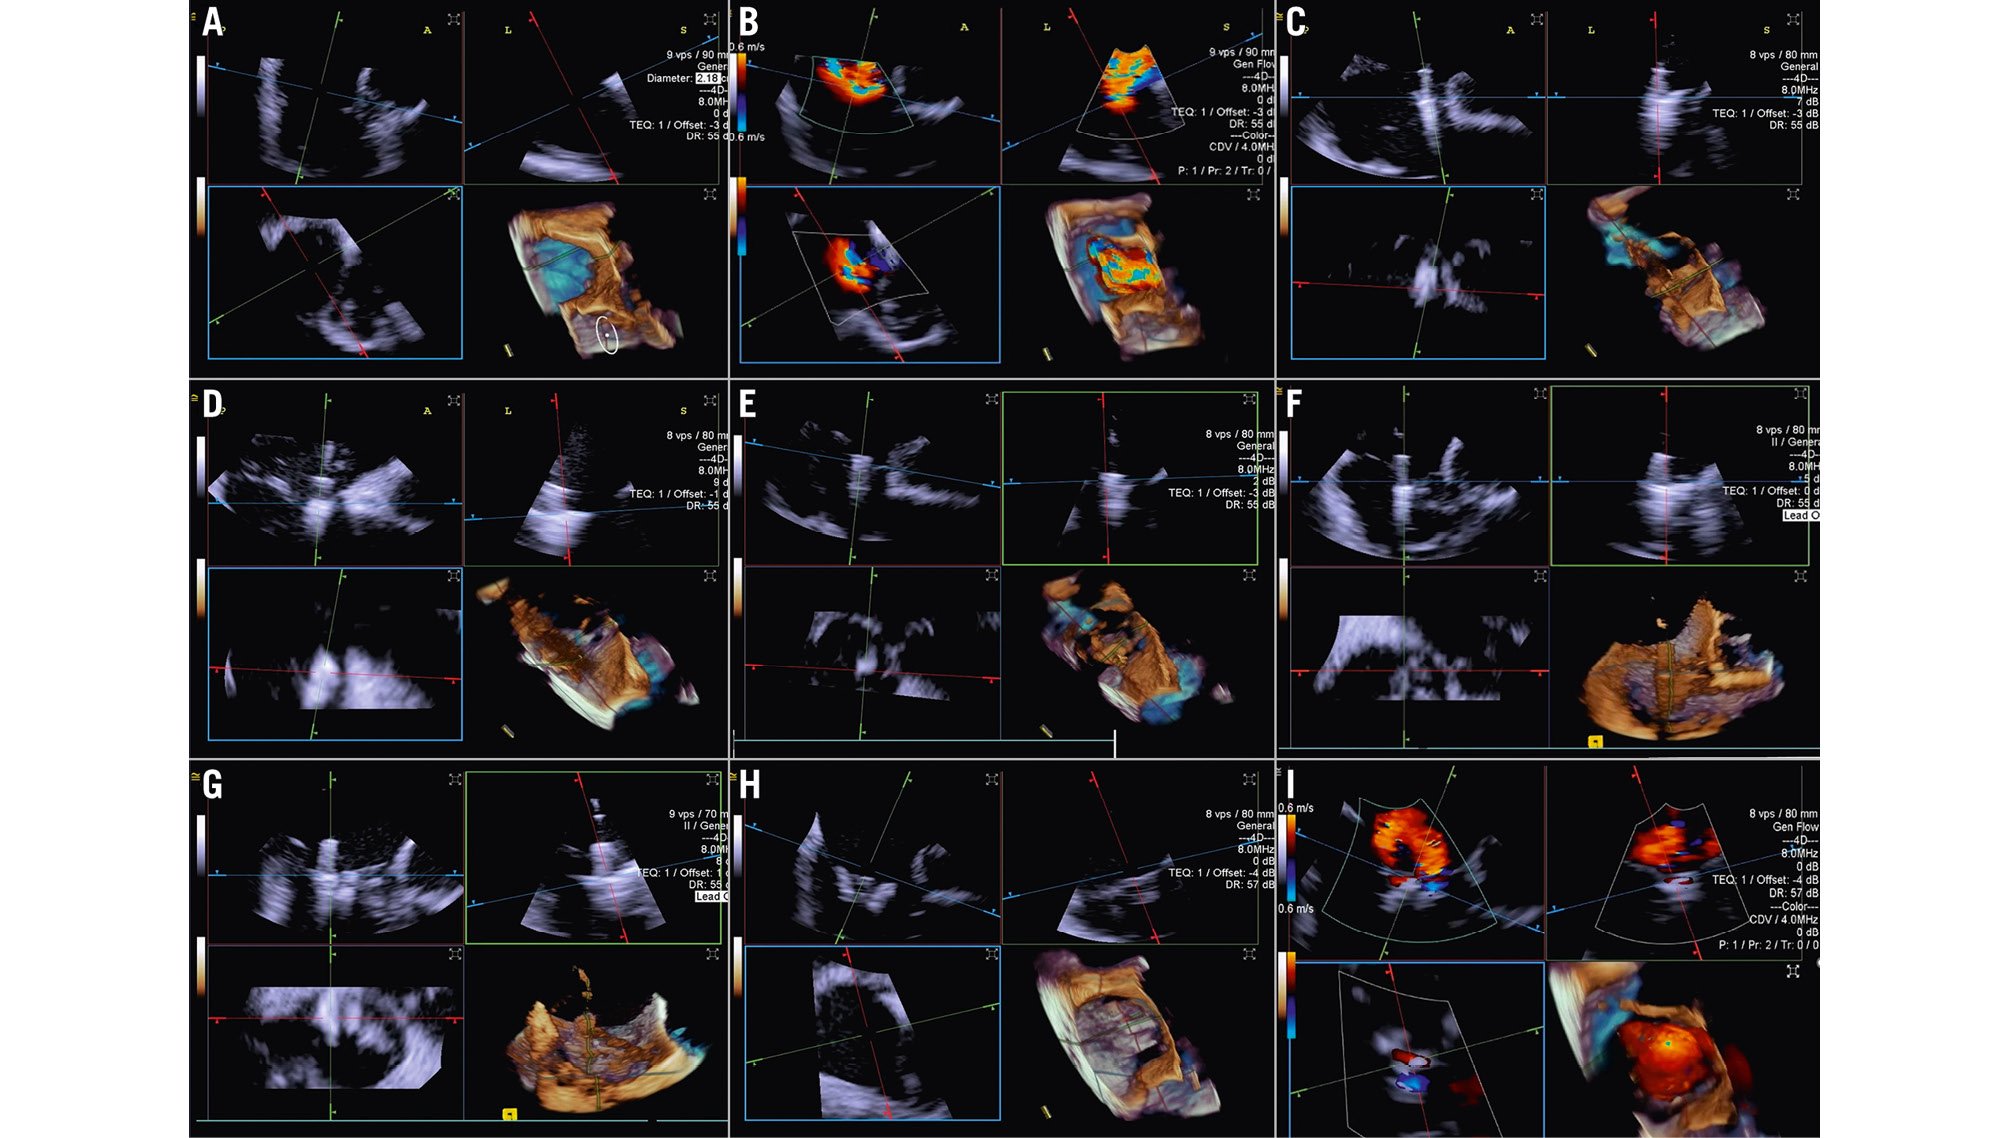

When performing a tricuspid TEER procedure (TriClip [Abbott], PASCAL [Edwards Lifesciences]), shadowing from mitral/aortic prostheses, septal hypertrophy, and other factors are particularly problematic when assessing for leaflet insertion. Three-dimensional ICE is a useful alternative for leaflet insertion in edge-to-edge repair. Starting from the home view (right ventricular inflow view), the use of biplane imaging creates a potential grasp view. Subsequently, a live 3D volume image can be obtained and used for a live 3D MPR16. Similar to TOE, 3D ICE also can be used for trajectory and alignment (Figure 4, Moving image 2-Moving image 3-Moving image 4-Moving image 5-Moving image 6-Moving image 7).

Figure 4. Three-dimensional ICE-guided tricuspid transcatheter edge-to-edge repair. A) 3D MPR ICE imaging planes with posterior and anterior leaflets in the TV home view (top left), septal leaflet and anterior/lateral grasping view (top right). The blue plane (bottom left) represents the short-axis (atrial en face) view of the TV leaflets. Finally, the corresponding 3D volume (bottom right; the aorta is at 5 o’clock). B) 3D colour MPR ICE imaging shows severe tricuspid regurgitation, allowing assessment of the number of regurgitation jets and jet location. C-E) The first device is advanced under the tricuspid valve. Clip orientation is optimised to be orthogonal to the coaptation line while the clip position is fine-tuned to the target location, and independent leaflet grasping is performed. F) 3D MPR assessment of second device orientation and location. G) 3D MPR assessment of third device orientation and location. H, I) 3D MPR and colour-flow Doppler final assessment of the devices. 3D: three-dimensional; ICE: intracardiac echocardiography; MPR: multiplanar reconstruction; TV: tricuspid valve